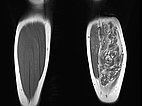

In der koronaren nativen T1-gewichteten Kontroll-MRT sind die Gefäßanteile der Läsion deutlich weniger abgrenzbar. Es bleibt jedoch deutlich zusätzliches Gewebe bestehen („Salz-und-Pfeffer-Muster“), zum Teil hyperintenses Fettgewebe, zum Teil hypointenses Bindegewebe. Dies ist typisch für eine Fibro-adipose Vascular Anomaly (FAVA).

Auch in der axialen Kontroll-MRT in T2-Wichtung sind die Gefäßkanäle zum großen Teil verschlossen. Nach erfolgreichem Verschluss bleibt aber ein schwarz-weißes „Salz-und-Pfeffer-Muster“ bestehen, das typisch für eine FAVA ist. Es besteht aus Fettgewebe (hyperintens) und Bindegewebe (hypointens).